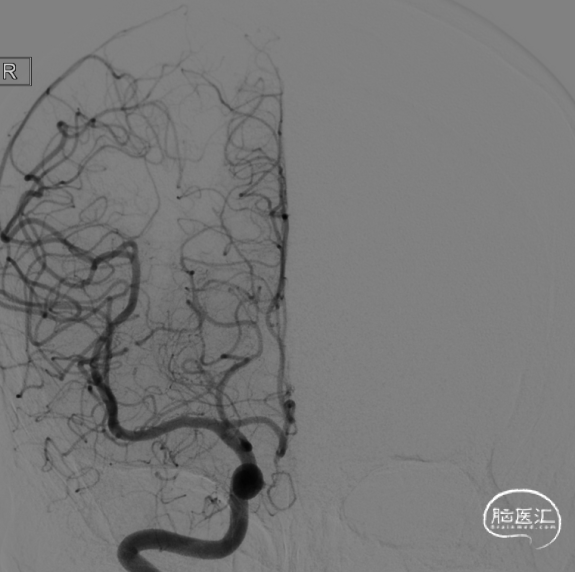

术前脑血管造影右侧颈内动脉眼动脉段多发动脉瘤。

左侧颈内动脉眼动脉段动脉瘤,呈囊状,大小约6.42×5.31×2.65mm,瘤颈4.32mm,颈内动脉直径约4.66mm,瘤体指向内后外方。